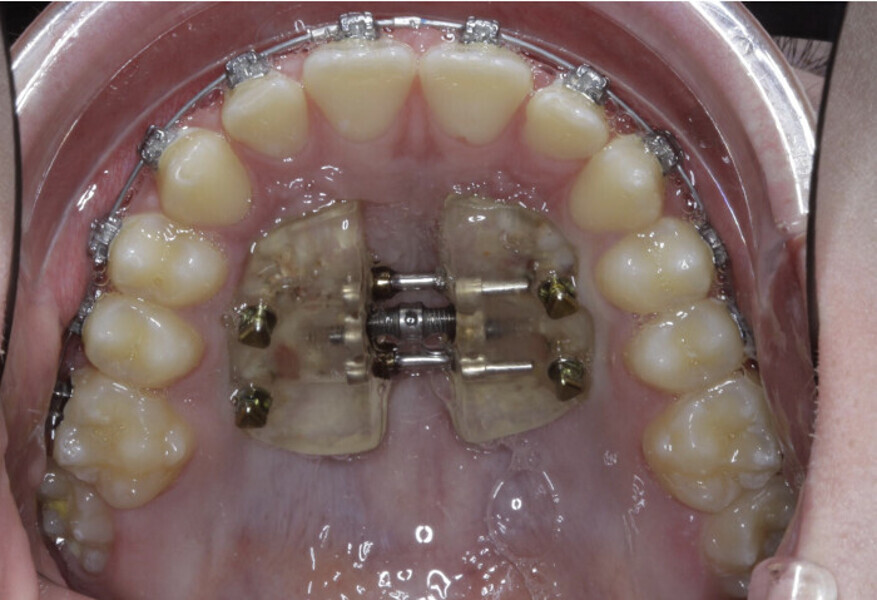

New Age orthodontics and orthopaedics with temporary anchorage devices